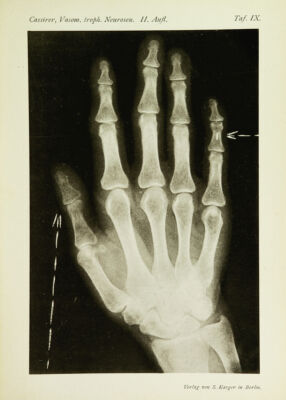

Die vasomotorisch-trophischen Neurosen : eine Monographie / von R. Cassirer.

- Cassirer, Richard, 1868-1925.

- 1912

Credit: Die vasomotorisch-trophischen Neurosen : eine Monographie / von R. Cassirer. Source: Wellcome Collection.